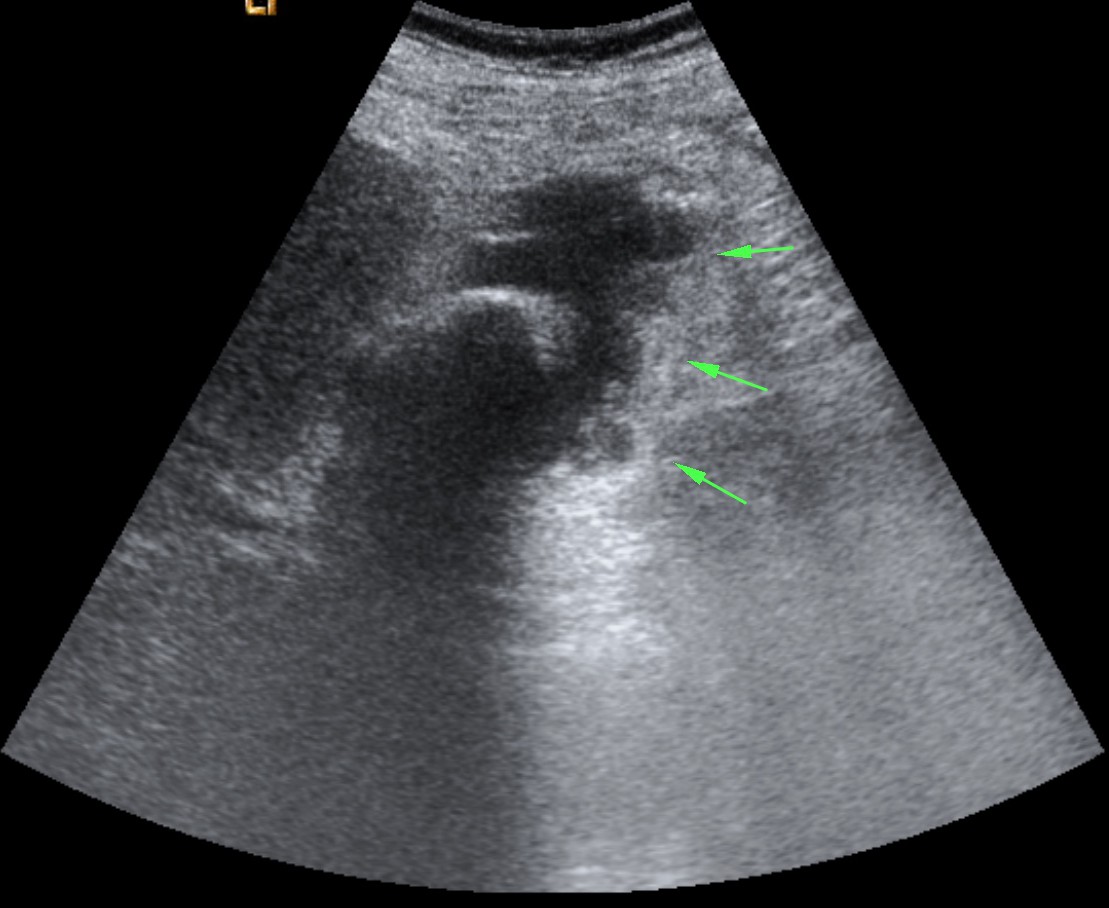

En sucesivos cortes observamos lo siguiente:

Se observa una mala evolución radiológica. Dada la clínica del paciente y los hallazgos ecográficos podemos concluir que estos hallazgos son compatibles una colecistitis xantunogranulomatosa litiásica sobreinfectada (que se confirmó posteriormente con anatomía patológica).

- Colecistitis xantunogranulomatosa: nódulos o bandas intramurales. Se producen por la oclusión de los senos de Rokitansky Aschoff de la pared, los cuales se rompen, luego la bilis coloniza la pared y finalmente produce una reacción inflamatoria a la que puede sobreañadirse una infección. Es un factor de riesgo para el carcinoma.

- Eco y TC: Litiasis + engrosamiento mural focal o difuso. Puede haber cambios inflamatorios pericolecísiticos. Los nódulos hipocogénicos o bandas pueden sugerir el diagnóstico específico de c. xantunogranulomatosa.

- El diagnóstico raramente se realiza previo a la cirugía y al análisis histopatologíco.